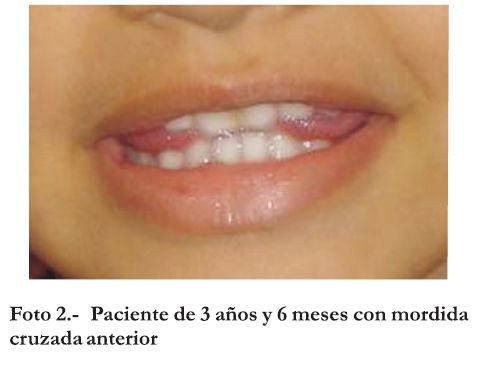

En la siguiente consulta de control anual, a los trea años y seis meses de edad (Foto 2), continúa la misma situación clínica, razón por la cual y al tener la paciente un crecimiento y desarrollo mayor se consideró oportuno solicitar una radiografía panorámica y una toma radiográfica oclusal del maxilar superior que permitieron identificar la presencia de dos elementos supernumerarios en la región anterior del maxilar superior.